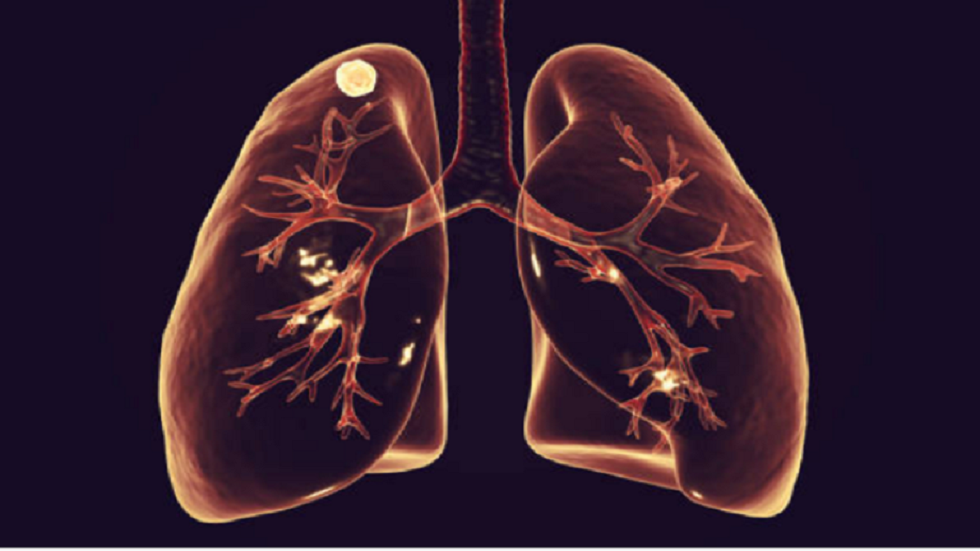

تحديد سبب ضعف استجابة سرطان الرئة للعلاج المناعي

اكتشف علماء معهد ماساتشوستس للتكنولوجيا سبب ضعف استجابة سرطان الرئة للعلاج المناعي. وأتضح أن البكتيريا التي تعيش في الرئتين تخلق بيئة تكبح نشاط منظومة المناعة.

وتشير مجلة Immunity، إلى أن العلاج المناعي هو الأكثر شيوعا في علاج أنواع معينة من السرطان، حيث يحفز الخلايا التائية على مهاجمة الخلايا السرطانية. هذه الطريقة فعالة في علاج أنواع معينة، لكنه يعطي نتائج مختلفة في حالة سرطان الرئة.

اختراق علمي يمكن أن يقلل من وفيات سرطان الرئة

واكتشف الباحثون خلال دراسة أجريت على الفئران المخبرية، أن تعطيل الخلايا التائية يحصل عندما يكون مستوى غاما إنترفيرون في العقد اللمفاوية المرتبطة بالرئتين مرتفعا. لأن إنتاج جزيء الإشارة يتم إستجابة لوجود انواع معينة من البكتيريا تعيش في جسم الإنسان دون التسبب في عدوى. ولكن لم يتمكن الباحثون من تحديد نوع هذه البكتيريا. ومع ذلك، عند حقنها بعقاقير تحجب غاما إنترفيرون، استعادت الخلايا التائية نشاطها.

ووفقا للباحثين، لغاما انترفيرون تأثير متعدد في منظومة المناعة، لذلك يمكن أن يؤدي حجبه إلى إضعاف الاستجابة المناعية الشاملة ضد الورم.

واستنادا إلى ذلك استنتج الباحثون أن استخدام العلاج المناعي في حالة سرطان الرئة ليس الاستراتيجية الأفضل. لذلك يأملون أن تساعد هذه النتائج على اكتشاف طرق جديدة لتعزيز الاستجابة المناعية لعلاج هذا النوع من السرطان.

المصدر: لينتاز رو